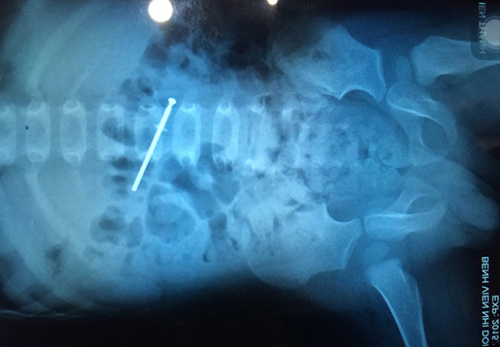

Phim Xquang ốc vít trong bụng cháu Th

Lúc này, anh nhớ lại hai cây đinh ốc vít nên tìm kiếm. Anh chỉ phát hiện được một cây rơi giữa đất còn một cây “mất tích”. Nghi ngờ con trai đã nuốt đinh ốc vít, gia đình liền đưa cháu đến trạm y tế. Sau đó, cháu được chuyển viện lên bệnh viện Nhi Đồng 1.

Sau khi khám, chụp Xquang, cháu được mổ bằng nội soi. Dị vật được lấy ra là đinh vít bằng nhôm dài 4,5 cm. Rất may, đinh ốc vít còn mới, nếu cũ thì nguy cơ nhiễm trùng rất cao.